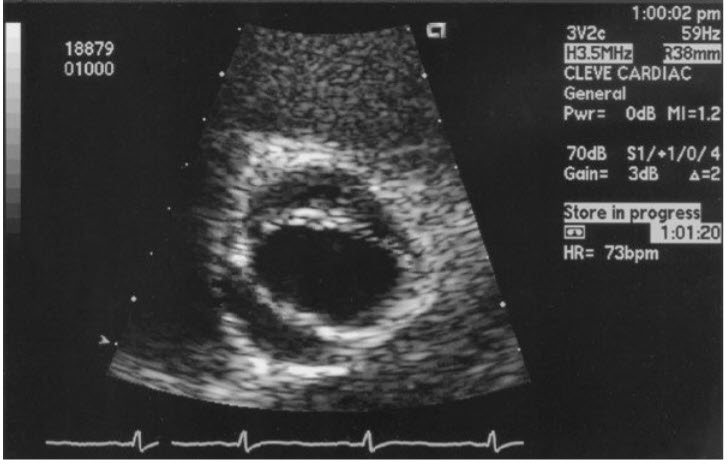

Match the following congenital cardiac disorder

Subaortic valve stenosis

with the characteristic transthoracic echocardiogram (TTE) finding in figures below:

a.

b.

c.

d.

e.